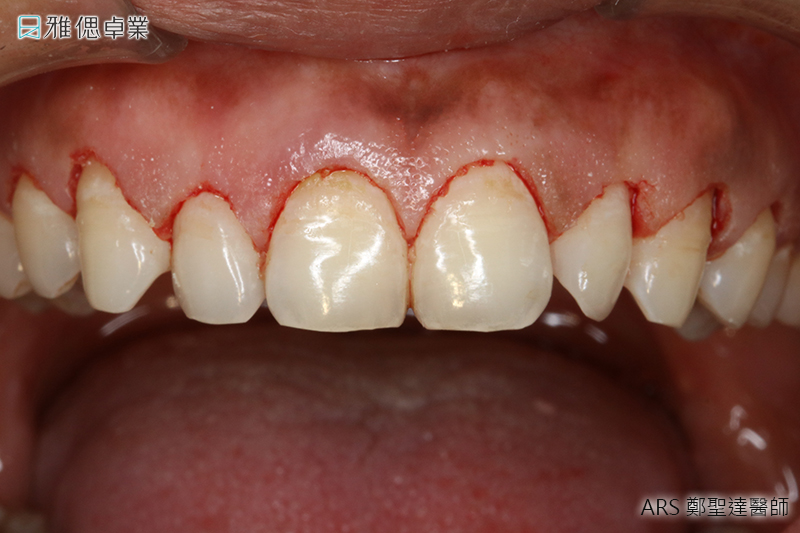

水雷射牙周手術

低疼痛牙周病快速治療運用水雷射新科技,能把全口牙周病治療時間縮短,術後復原時間比傳統開刀減少一半以上,殺菌力更佳,不需忍耐強烈術後腫脹等不舒適感,也可以減低害怕開刀的心理負擔。

牙周治療用水雷射處理牙周囊袋細菌

- 有效深入牙周囊袋清除發炎、潰爛組織

- 消滅細菌同時治療輕度牙齦炎

- 擁有卓越的殺菌效果

- 有效促進治療部位傷口癒合

- 降低牙周治療後腫痛不適感

- 大幅縮短牙周治療療程

- 無須翻開牙齦,增加治療舒適度

- 更有效深入清除發炎及潰爛組織

- 卓越的殺菌性促進術後復原

- 更有效地控制術後腫痛

- 大幅縮短治療程序

實際案例水雷射牙周病治療術前術後對照